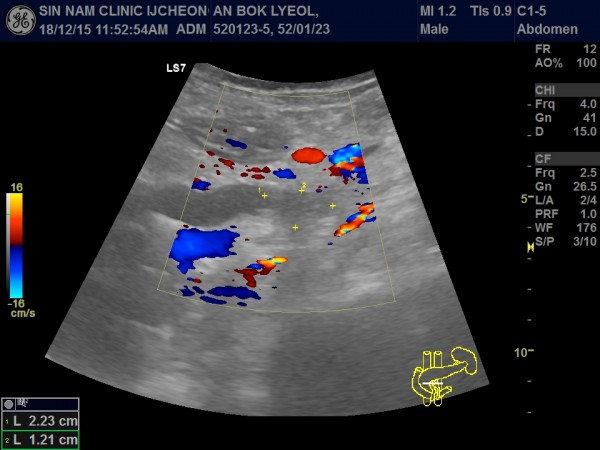

담관암, 담도암, 상복부 초음파